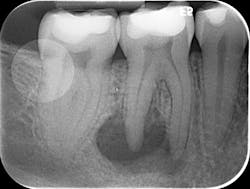

Various clinical presentations and risk factors can influence endodontic success or failure, including but not limited to the quality of the root canal performed and the seal of the coronal restoration.2 In addition to the aforementioned factors, the presence and size of a periapical lesion can directly affect the prognosis and treatment outcome. Classic literature highlights this shift in long-term success rates from 96% for vital/nonvital cases without the presence of a periapical lesion to 86% when a periapical lesion is present.3

Periapical radiographs have been commonly used to evaluate the size of periapical lesions. However, periapical radiographs have limitations, because the information is rendered in only two dimensions. A periapical lesion can only be detected in the radiograph when the mineral loss of bone reaches 30%–50%.4